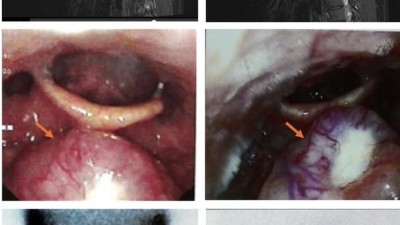

Return to flight in a helicopter pilot with lingual thyroid

Ectopic tissue at the tongue base was the sole functioning thyroid gland in a helicopter pilot incidentally diagnosed with lingual thyroid. Clinical stability, lack of symptoms, and treatment response, meant he was deemed fit to fly.

Fat cells 3D render/© Spectral-Design / Stock.adobe.com, Closed-loop insulin system on a pregnant woman/© dzika_mrowka / iStock / Getty Images Plus (symbolic image with model), Boy looking unhappy/© airdone / iStock / Getty Images Plus (symbolic image with model), Three darts in a dart board with one hitting the bull's-eye/© Richard Drury / Getty, Hand stacking three blue wooden blocks with green checkmarks/© izzuan / Stock.adobe.com, Supportive doctor with obese patient/© Halfpoint / Stock.adobe.com (symbolic image with models), High blood pressure diagnostics concept/© sudok1 / Getty Images / iStock, Colourful crowd of people (conceptual graphic)/© JuSun/Getty Images/iStock, Vitamin D capsules/© NiseriN / Getty Images / iStock, Thermal plantar foot images of a person with diabetes/© (M) 2024, N Christy Evangeline et al. in Big Data, Machine Learning, and Applications. BigDML 2021. Lecture Notes in Electrical Engineering, under exclusive license to Springer Nature Singapore Pte Ltd., CT scan of upper abdomen with contrast media/© Mdv Edwards / Stock.adobe.com, 3D rendered human spermatozoa/© Vink Fan / stock.adobe.com, Ophthalmologist pointing to a model of eye anatomy/© Drazen Zigic / Getty Images / iStock (symbolic image with models), 3D illustration of platelets in blood smear/© Kateryna_Kon / stock.adobe.com, Imaging of ectopic lingual thyroid/© 2025, Pangmin Li et al, BMC Endocr Disord (CC-BY-NC-ND), Paper kidneys with pills on pink background/© Pixel-Shot / stock.adobe.com, Zumba class in session/© FatCamera / Getty Images / iStock (symbolic image with models), Histology of patient with thyroid carcinoma, parathyroid adenoma, and paraganglioma/© 2025, Ankush Nayyar et al, J Med Case Reports, Hands reaching for donut/© Andriy / Stock.adobe.com, Dilated pupil/© Ivan-balvan / Getty Images / iStock